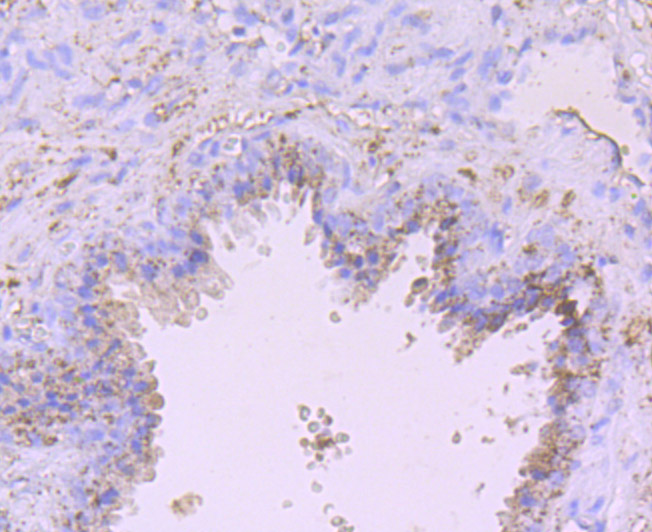

Catalog# ER1706-97

ADAM10 Rabbit Polyclonal Antibody

IHC-P

Human